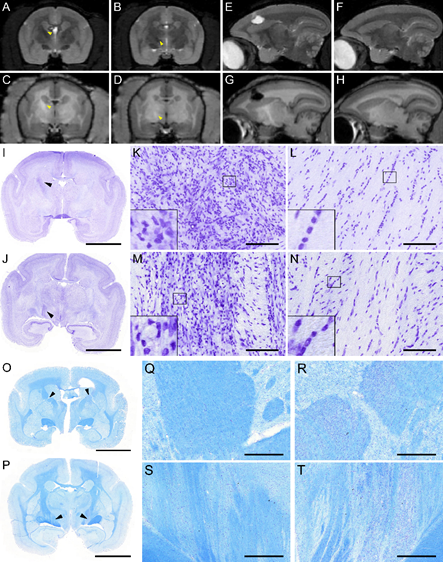

La création d’un modèle lésionnel comportant une hyperactivation des NMDA a permis de tester la capacité de la [18F] FNM à discriminer une zone d’hyperactivation d’une zone normale. Ce modèle a été réalisé sur des rats qui ont subit une injection intracérébrale d’excitotoxines agonistes du glutamate, provoquant une suractivation des récepteurs au glutamate et spécifiquement du récepteur NMDA. Cette expérimentation nous a permis d’évaluer la capacité du radiotraceur à discriminer une hyperactivation des récepteurs NMDA par comparaison de l’hémisphère sain et de l‘hémisphère lésé.

Nous avons pu ainsi visualiser la cinétique des activations de récepteurs NMDA après lésion (J0, J+1, J+3, J+5). Grâce au traitement d’image et à l’analyse voxel à voxel sur le logiciel spm , nous avons fait un « template » de cerveaux de rats sain et nous avons pu comparer les rats lésés à ce template. Nous avons pu constater que l’on pouvait discerné la zone lésée avec la FMN mais que les zones hyperactives évoluent avec le temps avec une activation importante de la zone perilesionnelles précoce et une activation de zones en réseaux avec la zone lésé plus tardive.

La transfection a d’abord été mise au point sur des cellules neuro2a avec un plasmide contenant le gène de la TK et un gène de résistance à la néomycine permettant leur sélection. Nous avons ensuite mesuré le pourcentage de [18F]-FHBG capté par ces cellules et nous l’avons comparé à la captation par des cellules non transfectées. Le pourcentage de captation des cellules transfectées est 10 fois supérieur à celui des cellules non transfectées. Nous avons réalisé une calibration in vivo : les cellules incubées dans le radiotraceur sont injectées de manière stéréotaxique dans les cerveaux de rats préalablement lésés. Les rats sont lésés à l’aide d’une toxine (Malonate 3M) injectée au niveau du cortex moteur à 2 mm de profondeur (coordonnées 2 mm latéral, 0 mm antérieur atlas de Paxinos). Nous avons pu ainsi suivre la qualité des injections et nous avons corrélé le nombre de cellules injectées avec l’intensité du signal émis en TEP.